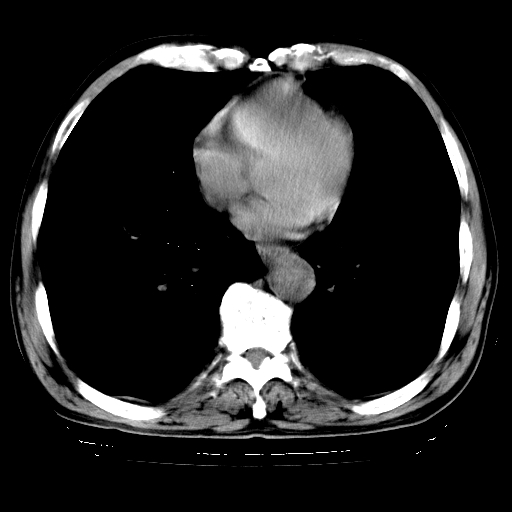

以下是引用hhcckk在2009-1-1 15:38:00的发言:[br]左下肺少许絮状模糊影--考虑感染[br]两肺散在小点状密度增高影--结合病史考虑矽肺?[br]气管壁钙化--可能由于老年退变性引起的